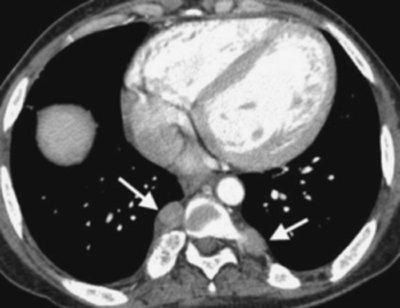

FIGURE 6-23. Pulmonary histoplasmosis. A: PA chest radiograph shows right paratracheal (solid arrow) and bilateral hilar (dashed arrows) lymphadenopathy. B: CT scan shows bulky right paratracheal lymphadenopathy (arrow). C: CT scan at a more inferior level shows bilateral hilar (solid arrows) and subcarinal (dashed arrow) lymphadenopathy. The appearance is indistinguishable from that of sarcoidosis.